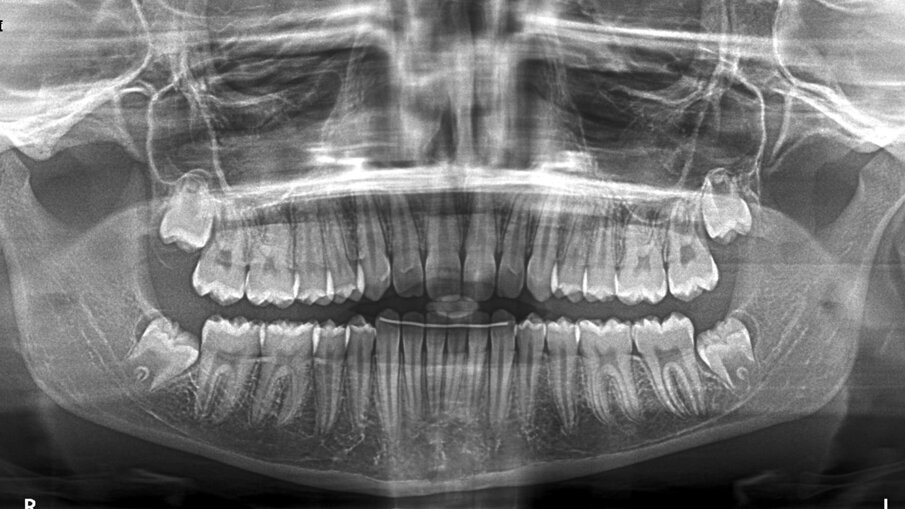

All’esame obiettivo intraorale si riscontra sul piano frontale un severo morso profondo con precontatto traumatico degli incisivi superiori contro la papilla retroincisiva e le rughe palatine anteriori durante la massima intercuspidazione, con overbite di 10 mm (Fig. 5). Dalle foto laterali si evidenzia una malocclusione di Classe II divisione 2 con scissor bite dell’elemento 1.5 (Figg. 6, 7), mentre dalle foto occlusali si rileva un grave affollamento con contrazione di entrambe le arcate maggiore nella zona premolare (Figg. 8, 9). L’analisi di Bolton mostra un eccesso superiore 3-3 di 2,34 mm (73,6%) e 6-6 di 2,76 mm (88,8%). L’analisi cefalometrica evidenzia una Classe II scheletrica, modello facciale normodivergente, angolo interincisale aumentato, incisivi superiori e inferiori retroinclinati (Fig. 10). La radiografia panoramica mostra la presenza dei germi dei terzi molari, assenza di parallelismo tra le radici dei premolari inferiori (Fig. 11) e una sovraeruzione degli incisivi inferiori che crea un doppio piano tra gli incisivi e i molari, segno di una curva di Spee molto profonda.

Fig. 11_Ortopantomografia pre-trattamento.

La durata totale del trattamento è stata di 12 mesi, il risultato è stato ottenuto grazie a una pianificazione computerizzata dettagliata e a scelte terapeutiche accurate, unite a una biomeccanica appropriata per la malocclusione nei tre piani dello spazio. Il sorriso della paziente ha ottenuto un miglioramento estetico evidente, con il riempimento dei corridoi buccali, una corretta esposizione degli incisivi e un miglioramento del profilo grazie alla proiezione del pogonion cutaneo e alla coincidenza delle linee mediane (Figg. 14-17). I dati clinici finali evidenziano un rapporto bilaterale di Classe I ottenuto grazie al preciso timing di inizio della terapia. Sono stati normalizzati gli eccessi di overjet (2,5 mm) e overbite (2,5 mm), risolvendo così il severo morso profondo (10 mm) e correggendo la curva di Spee. In entrambe le arcate è stato ottenuto un buon allineamento dentale, il ripristino della forma dell’arcata e la correzione dello scissor bite (Figg. 18-23). Le relazioni scheletriche sagittali sono migliorate con una normalizzazione del rapporto sagittale mandibolare A-N-B a 4° e un indice di Wits di 2 mm. Da un punto di vista delle relazioni verticali, l’inclinazione mascellare è rimasta pressoché invariata, così come l’inclinazione mandibolare. Per quanto riguarda i rapporti dento-basali, l’inclinazione degli incisivi è migliorata rientrando nei valori fisiologici. In termini di rapporti dentali, i valori mostrano la correzione dell’overjet e una variazione positiva dell’overbite (da 10 mm a 2,5 mm). Anche l’angolo interincisale è migliorato di 29°, spostandosi da 158° a 129° (Tab. 1, Fig. 24). La radiografia panoramica mostra il raggiungimento di un buon parallelismo radicolare (Fig. 25) e la correzione del doppio piano tra incisivi e molari. Al termine del trattamento alla paziente è stato applicato uno splintaggio fisso inferiore 3-3 e le sono stati forniti retainers di contenzione Vivera customizzati con Precision Bite Ramp al fine di promuovere la stabilità dei risultati ottenuti a lungo termine.